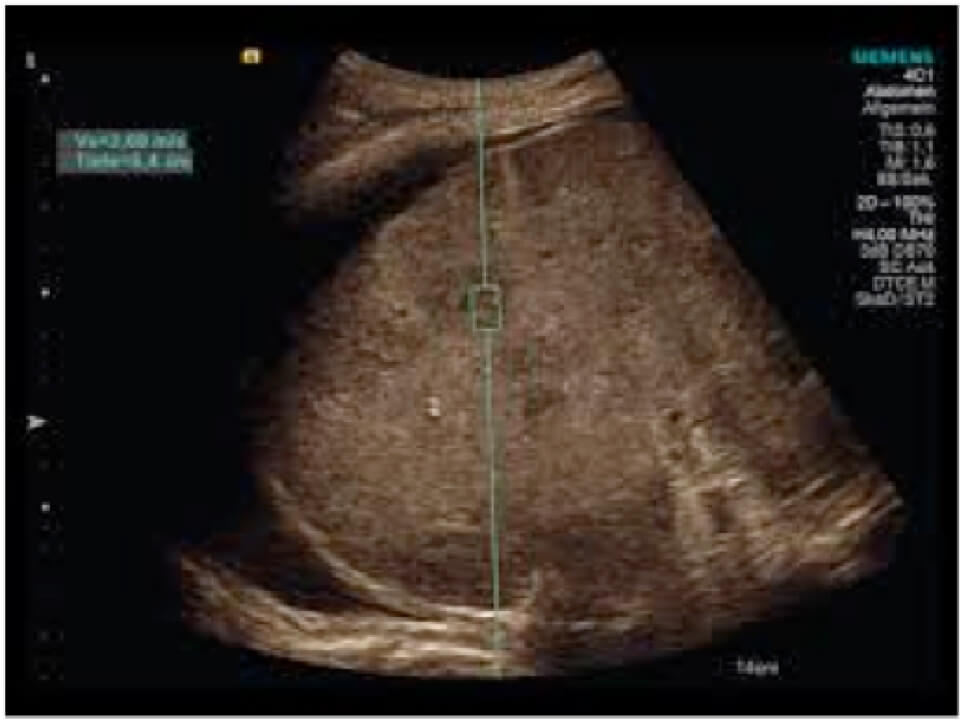

NEUESTE TECHNIKEN IN DER ULTRASCHALLDIAGNOSTIK

Das Leberpaket des Siemens Acuson S 2000 Helx Evolution Ultraschallsystem kombiniert modernste Bildgebungsmodalitäten für Screening, Diagnostik, Staging und das

Monitoring von Lebererkrankungen. Mit dem Elastographiemodul ist es möglich nichtinvasiv Stadien der Leberfibrose zu erfassen. CEUS, ist auch ein neues Verfahren, wo

mit speziellen Ultraschallgeräten besondere Kontrastmittel, sogenannte „Echosignalverstärker“, verwendet werden können. Da sie kein Jod enthalten, führen sie nicht zu

den vom Röntgen bekannten allergischen Reaktionen und können auch bei bekannter Kontrastmittel- oder Jodallergie eingesetzt werden. Der Einsatz von Ultraschall-

Kontrastmitteln hat zum Beispiel den Nachweis von kleinen Lebertumoren verfeinert. Auch die Unterscheidung zwischen gutartigen und bösartigen Tumoren ist dadurch

treffsicherer und kann vielen Patienten eine Punktion ersparen.

Elastograhie-Fibroscan

Eine chronische Lebererkrankung egal welcher Genese, ob durch Alkohol, Hepatitis-Viren, Stoffwechsel- bzw. Autoimmunerkrankungen, Fettleber, Chemikalien bzw.

Medikamente bedingt, kann zu einer Leberzirrhose führen. Die Leberzirrhose, das ist ein knotiger Umbau der Leber, dies ist bedingt durch Untergang von Leberzellen,

die durch Narbengewebe ersetzt werden. Bis ein kompletter Umbau stattgefunden hat durchläuft die Leber verschiedene Stadien mit Narbenbildung, den sogenannten

Fibrosestadien.

Die frühzeitige Erkennung der Fibrose ist wichtig um therapeutische Maßnahmen zu ergreifen, die das Voranschreiten der Grunderkrankungen stoppen sollen. Die

betroffenen Patienten merken in der Regel nichts von ihrer Erkrankung, auch im fortgeschrittenem Stadium ist die Leberzirrhose schmerzfrei. Die beginnende Zirrhose ist

durch die üblichen bildgebenden Verfahren (CT, MRT, Sonographie) aber auch durch Bluttests in der Regel nicht erkennbar. Die bisher übliche und weit verbreitete

Maßnahme der Fibroseerkennung war die Leberpunktion, bei der mittels einer Nadel Lebergewebe entnommen und hiernach feingeweblich (histologisch) untersucht

wurde, dieses Verfahren erlaubt eine ziemlich exakten Beurteilung der Leber bezüglich des Fibrosierungsgrades, d.h. das Ausmaß der Leberschädigung.

Ein neues sogenanntes Elastographieverfahren, was unserer Praxisklinik seit 1 Jahr zur Verfügung steht, erlaubt uns nicht invasiv, schmerzfrei auf sanfte Art den Ausmaß

der Leberschädigung abzuschätzen, dieses erfolgt durch Messung der Leberelastizität, die bei zunehmender Vernarbung abnimmt. Die Untersuchung erfolgt ambulant mit

einem speziellen Schallkopf, der in Leberhöhe auf der Haut aufgesetzt wird. Im High-Tech-Verfahren wird über Schallwellen die Verformbarkeit der Leber gemessen und

als quantitativer Wert in der Einheit Kilopascal (Kpa) angegeben. Die Elastographie ist auch Ideal um den Verlauf einer chronischen Lebererkrankung zu beurteilen.